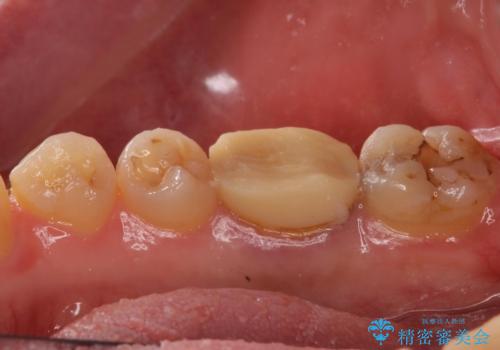

- 右下の奥歯がうずくとのことで来院されました。

根管治療を行った後、セラミックのかぶせ物を装着します。